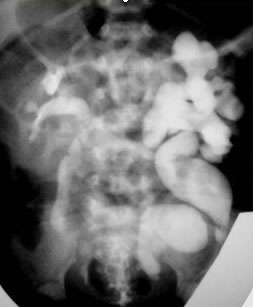

Продемонстрированы слайды с фотографиями и ренгеновскими

снимками патологий, приводящих к развитию функциональных

нарушений мочевого пузыря и мегауретеру. Для выявления пузырно-зависимой

До лечения: